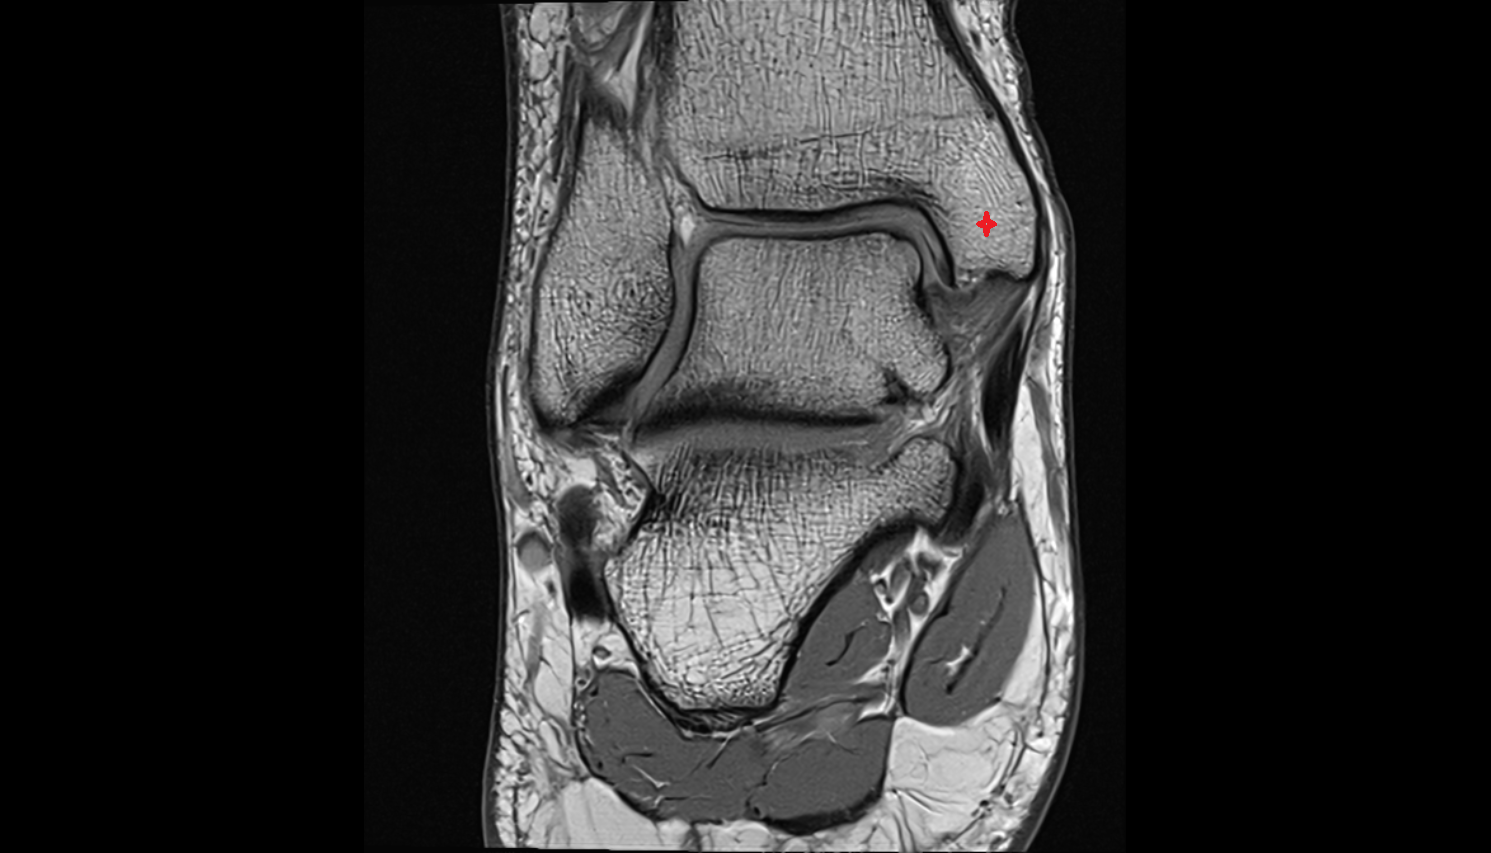

- Knee Joint